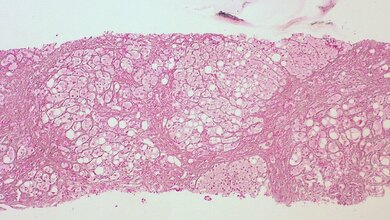

Forscher des Deutschen Zentrum für Diabetesforschung (DZD) haben aus klinischen Daten einen neuen Index generiert, der mit hoher Genauigkeit das Vorliegen einer Fettlebererkrankung vorhersagen kann. Etwa jeder dritte Erwachsene in den industrialisierten Ländern hat eine krankhaft verfettete Leber. Damit erhöht sich für diese Menschen nicht nur das Risiko an fortgeschrittenen Lebererkrankungen wie Leberzirrhose und Leberkrebs, sondern vor allem auch an Typ-2-Diabetes und Herz-Kreislauferkrankungen zu erkranken.

Um frühzeitig mit präventiven und therapeutischen Maßnahmen intervenieren zu können, muss die Fettleber rechtzeitig erkannt werden. Hierfür sind die Ultraschalluntersuchung der Leber und die Bestimmung der Leberwerte zwar geeignet, sie können die Fettleber aber meist nur in einem fortgeschrittenen Stadium diagnostizieren. Aufwändigere Untersuchungen wie die Kernspinspektroskopie sind hierfür zwar aussagekräftiger, sie sind aber wegen der relativ hohen Kosten im klinischen Alltag nicht auf breiter Ebene einsatzfähig. Daher arbeiten Wissenschaftler weltweit an einfachen und genauen Methoden, die für die Diagnose einer Fettleber besser geeignet sind. Unter verschiedenen Indizes, die dafür entwickelt wurden, hat sich der ‚Fatty Liver Index‘ (FLI) bestehend aus den Parametern Alter, Body-Mass-Index, Taillenumfang und den im Nüchternzustand im Blut gemessenen Werten für Triglyzeride (TG) und Gamma-Glutamyltranspeptidase (GGT), als recht effektiv erwiesen.